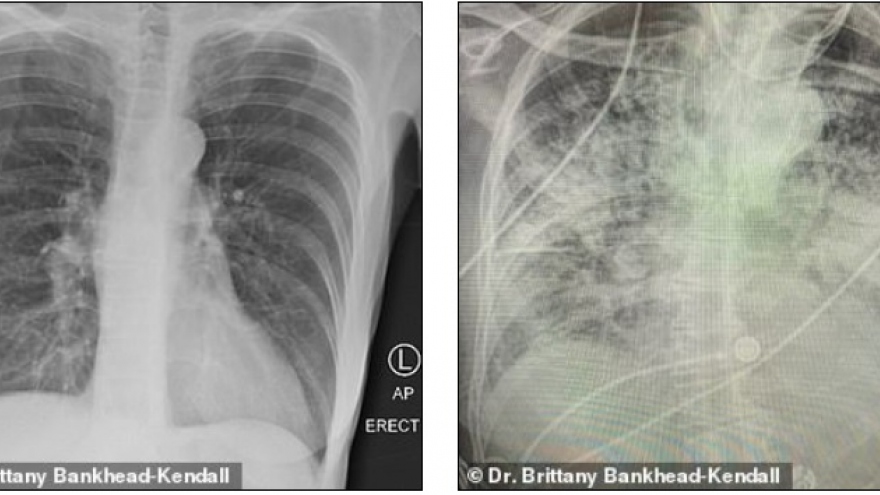

Sốc về mức độ tàn phá hai lá phổi của Covid-19

VOV.VN - Phát hiện mới đây cho thấy phổi các bệnh nhân sau khi mắc Covid-19 còn tệ hại hơn phổi của những người nghiện thuốc lá nặng. Phổi bệnh nhân Covid-19 bị tổn hại và có nhiều sẹo nặng.